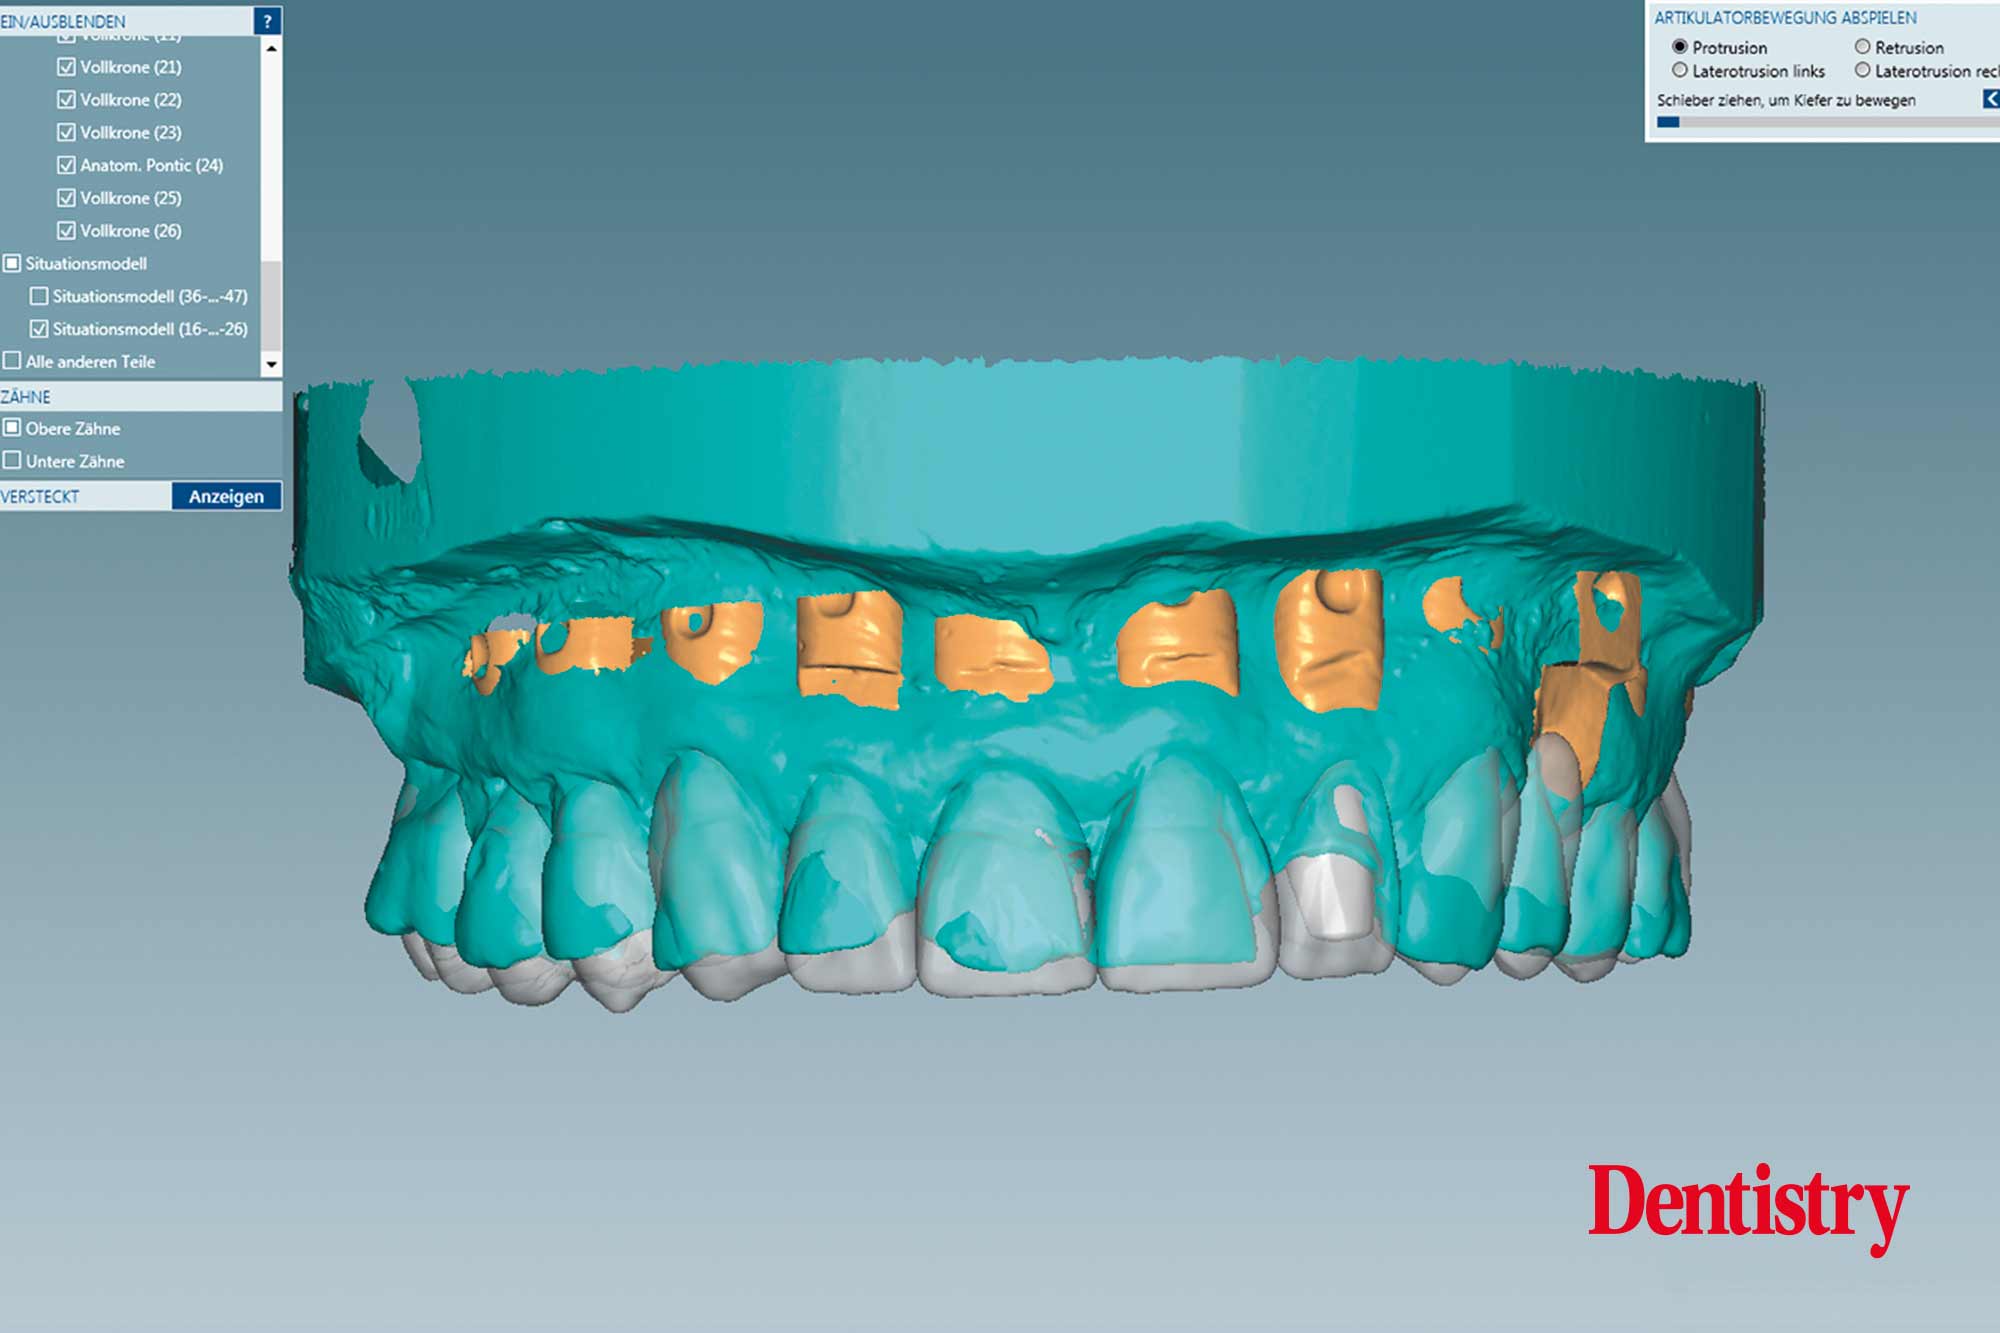

The scanned models were evaluated on a virtual 11 articulator. Temporary Ceramill PMMA (Amann Girrbach) transparent acrylic crowns were CAD planned (Figures 3a to 3d).

All patient parameters including condylar inclination were transferred to the Ceramill Artex articulator and the lateral and protrusive excursions were established while having no contact with the anterior teeth (Figures 5 to 8).

The virtual temporary crowns were 3D printed and then temporarily cemented. This test phase with temporary crowns is a mandatory step because after the patient evaluated the temporary crowns for several weeks, corrections were made with the input of the patient, thus reducing the risk of errors in the subsequent final crowns.